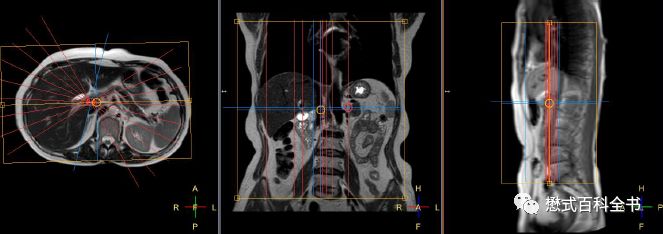

如果单独扫描MRCP,我们除了扫描定位像,首先需要扫描一个冠状位的T2WI好作为参考。最好再推荐扫描一个T2脂肪抑制的横轴位,这样MRCP的定位就更准确了。

定位的时候,在冠状位和横轴位上面一起定MRCP扫描的角度。

图17:MRCP的定位